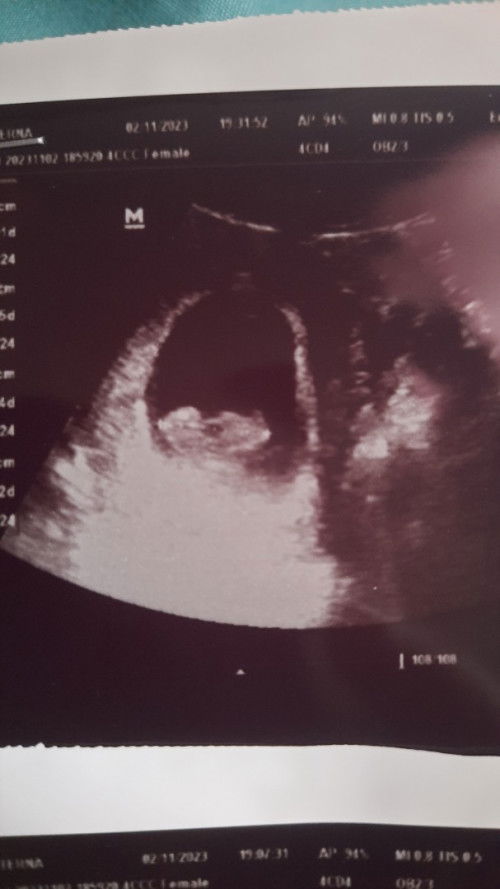

Hamil 10 week blm terdengar detak jantung

Halo bunda2, saya mau tanya, usia kandungan menurut hpht saya 10w1d, tp menurut usg masih sekitar 8-9w. Kemarin saya usg di klinik bidan, tapi belum bisa mendengar djj nya. Waktu awal usg 5w itu masih kantung. Lalu 10w saya usg lg sudah ada janin dan saya melihat janin saya lebih berkembang dr sebelum nya. Saya tidak ada keluhan seperti flek, hanya kadang kram nyeri tp tidak sering dan tidak sakit. Juga keputihan tapi masih keputihan biasa bun. Kira2 bagaimana yaa menurut bunda2 disini? Ini kehamilan anak pertama dan terus terang saya merasa cemas, khawatir dan tidak tenang bun. Terimakasih